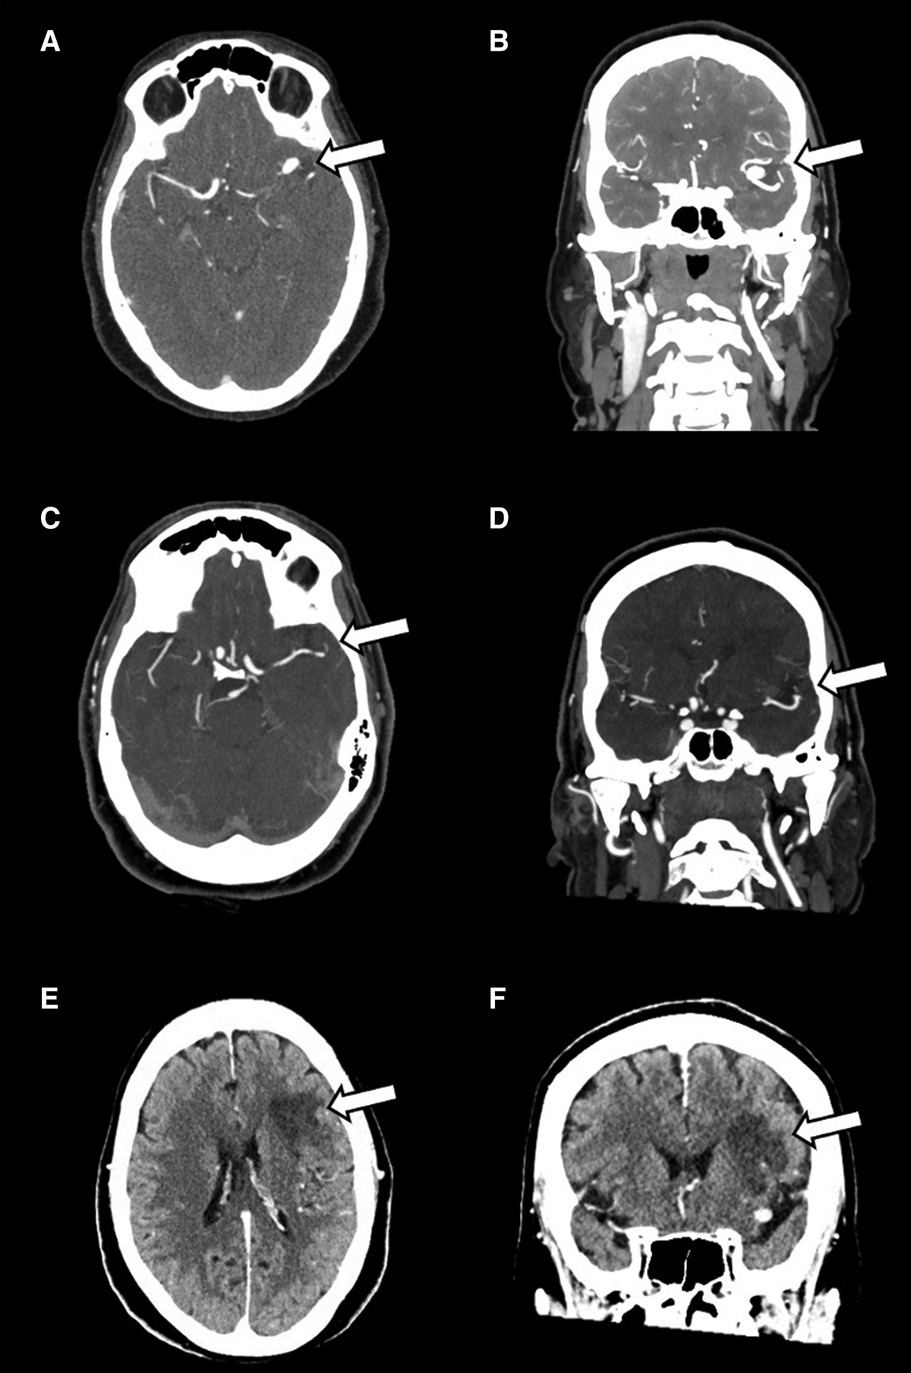

图e和f,左侧m2上干梗死:平扫ct可见mca局部高密度信号为动脉瘤内血栓